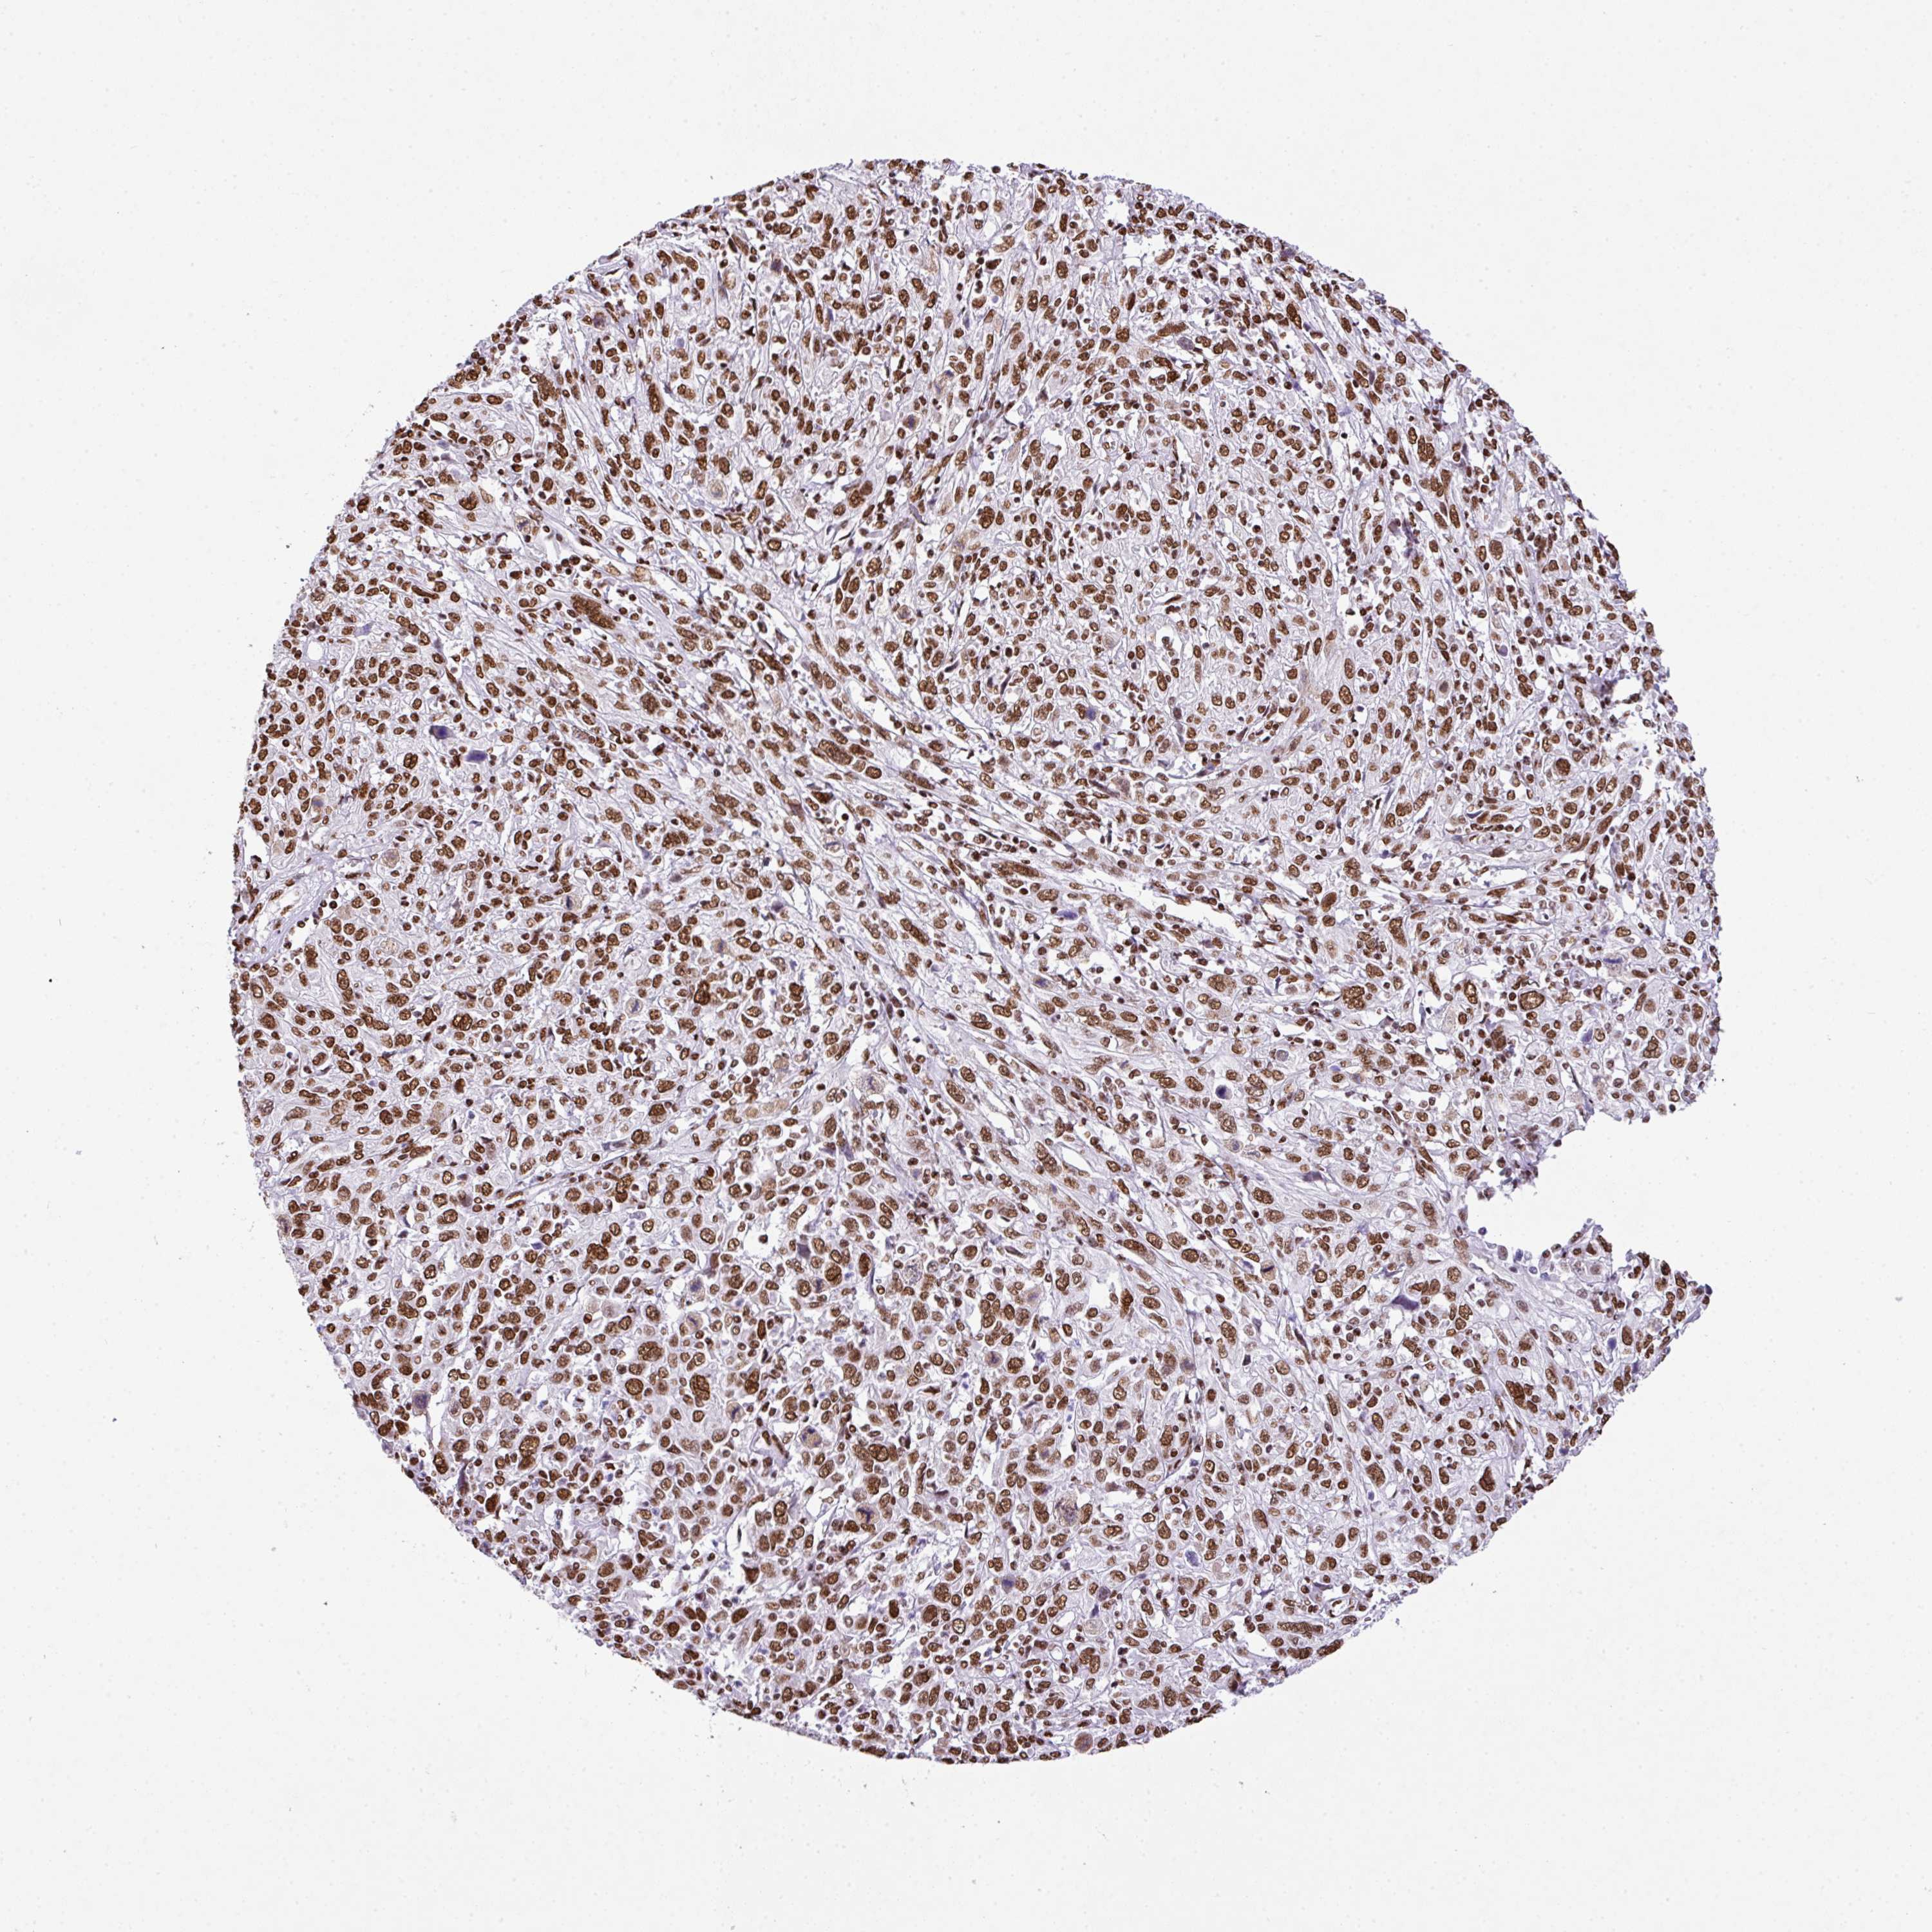

CERVICAL CANCER - Protein expressioni

A mouse-over function shows sample information and annotation data. Click on an image to view it in a full screen mode. Samples can be filtered based on level of antibody staining by selecting one or several of the following categories: high, medium, low and not detected. The assay and annotation is described here.

Note that samples used for immunohistochemistry by the Human Protein Atlas do not correspond to samples in the TCGA dataset.

Antibody stainingi

Antibody staining in the annotated cell types in the current human tissue is reported as not detected, low, medium, or high, based on conventional immunohistochemistry profiling in selected tissues. This score is based on the combination of the staining intensity and fraction of stained cells.

Each image is clickable and will lead to virtual microscopy that enables deeper exploration of all samples and also displays staining intensity scores, fraction scores and subcellular localization as well as patient and tissue information for each sample.

Antibody HPA053883

Staining

High

Medium

Low

Not detected

Intensity

Strong

Moderate

Weak

Negative

Quantity

>75%

75%-25%

<25%

None

Location

Nuclear

Cytoplasmic/membranous

Cytoplasmic/membranous,nuclear

Squamous cell carcinoma, NOS